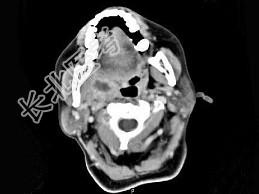

- 单项选择题女,52岁, 咽喉部疼痛半个月,伴低热, CT如图所示,最可能的诊断是 ( )

A、咽旁脓肿

B、咽部神经鞘瘤

C、鼻咽纤维血管瘤

D、咽旁淋巴瘤

E、咽旁转移瘤